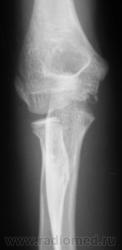

Перелом шейки луча без смещения.

Я не знаю александра александровича, но думаю по зонам роста -он молодой человек. + ко всему вышесказанному добавлю эпифизиолиз головки луча, перелом мыщелков плеча, ну и отмеченные вами шейка луча и локтевой отросток. Далее в проекции м/тканей , с латеральной стороны определяется отломок ? обызвествлённая связка?- в последнем случае это может быть старая ( м.б спортивная?) травма

Эпифизеолиз медиального вала блока плечевой кости + эпифизеолиз головки лучевой кости.

Снят ГИПС. Пациентка направлена на контрольную рентгенографию.

да медиальный надмыщелок не стоит на месте

А где же он стоит? как раз на месте. Сломана была шейка луча.

на1-2мм ниже. но это не принципиально, главное как локоть работает клинически.